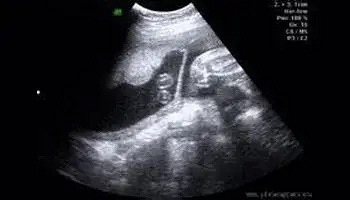

一下子完成任务了,不知道这位孕妈,内心到底是惊喜还是焦虑

一下子完成任务了,不知道这位孕妈,内心到底是惊喜还是焦虑。